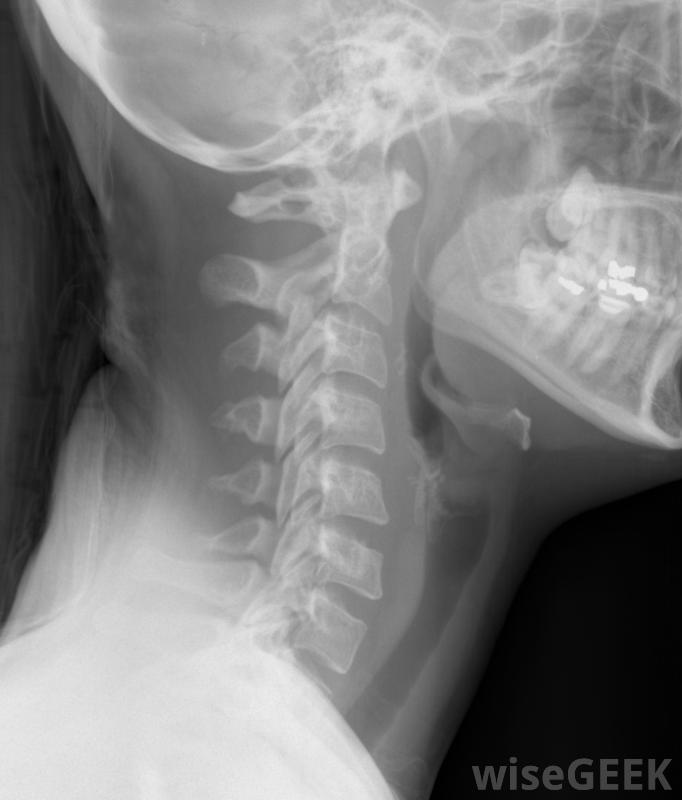

包括颈椎在内的颈部X光片。包括哪些内容这个区域作为一个整体有时可以被认为是颈部和上半身,至少就脊柱而言是这样的。因此,它由几个重要的组成部分组成:比如韧带、肌肉和关节。神经系统起着重要的作用,不仅所有的肌肉和关节都有神经末梢,脊柱也是人体许多最大神经的通道和保护鞘,作为外周神经系统的枢纽,第一块椎骨,阿特拉斯椎骨,以神话中的地图集命名鉴别椎骨颈椎区域的椎骨不同于其他脊椎区域的椎骨,因为每个区域都有向大脑输送血液的开口。重要的是,前两块椎骨的形状不同于另一块椎骨。第一块椎骨或C1椎骨支撑着头部的重量,并允许弯曲和伸展。这第一块椎骨有时也被称为阿特拉斯椎骨,以希腊神话中的泰坦命名,他在阿特拉斯山上的栖身之地支撑着天空

在人体解剖学中,颈椎是脊椎的上部,从头骨的正下方开始,止于胸椎的顶部。七个椎骨和分隔它们的椎间盘组成了这个区域,并以拉丁语单词"颈部"或"颈部"来统称。这些椎骨被命名为C1到C7就像向后的C,形成前凸曲线。脊柱的腰椎部分形成一个类似的曲线,而脊柱的胸椎和骶骨区域形成后凸曲线。正是这种相反的曲线结构有助于分配机械应力,不断地冲击脊柱